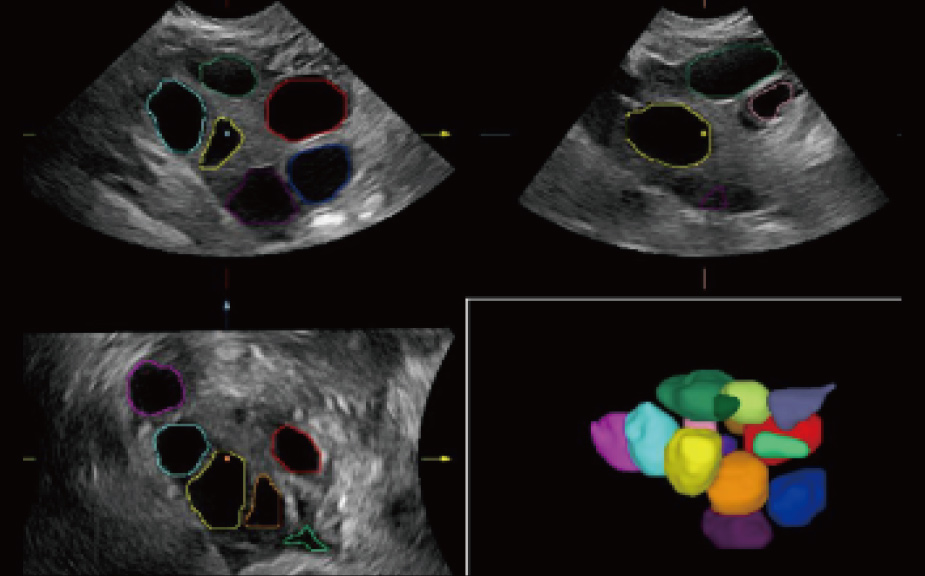

Intelligenza completa orientata allo scenario clinico

L'innovativa soluzione Smart Scene 3D consente l'identificazione automatica delle caratteristiche dei tessuti e fornisce una diagnosi specifica per i diversi distretti di esame durante l'intera procedura. Questa innovazione aumenta lŌĆÖaccuratezza e la sicurezza diagnostica, migliorando lŌĆÖefficienza.